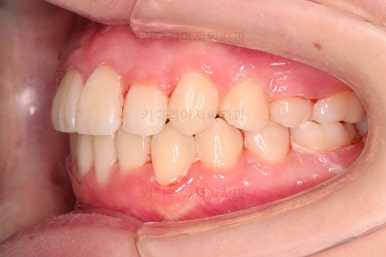

덧니도 개선되었고 가지런한 느낌도 좋네요.

교합도 좋고, 평행하지 않던 느낌도 많이 좋아졌습니다.

전후 사진을 보여드리겠습니다.

많은 부분이 좋아졌고요.

웃을 때 기울어져 보이던 치열의 모습도 좋아졌습니다.